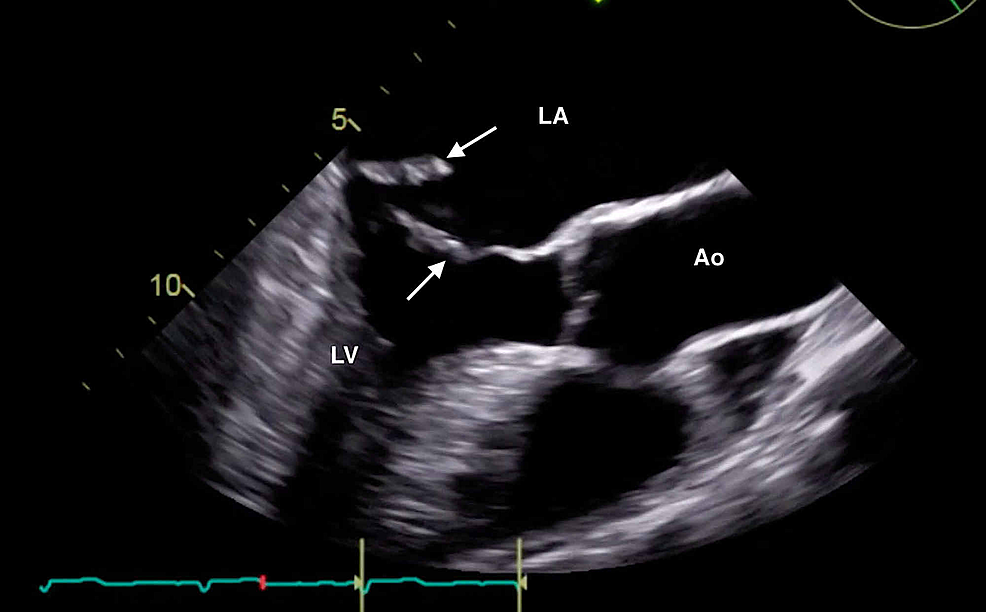

The clinical history was also concerning for an undiagnosed cardiomyopathy, particularly given the heart murmur appreciated on examination and his stated history of MVP for which the patient had never sought outpatient cardiology follow-up. Bedside LUS and FOCUS were then performed by emergency medicine resident physicians. LUS was notable for the presence of a diffuse B-line profile consistent with pulmonary edema (Figure 1). FOCUS was unremarkable for evidence of pericardial effusion, signs of right heart strain, or decreased LV contractility. However, FOCUS revealed a dilated left atrium (LA) and a suspected posterior FML, with the posterior MV leaflet seen protruding into the LA (Figures 2, 3; Videos 1, 2).

The constellation of FOCUS findings immediately prompted a formal comprehensive transthoracic echocardiogram (TTE) and emergent cardiology and cardiothoracic surgery consultations. TTE confirmed preserved LV systolic function, LA dilation, and flail motion of the posterior MV leaflet with severe eccentric MR (Figures 4, 5; Videos 3-5).